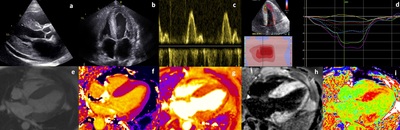

Cardiac Amyloidosis: Updates in Imaging

PURPOSE OF REVIEW: We summarize key features pertaining to the two most commonly encountered types of cardiac amyloidosis (CA), monoclonal immunoglobulin light chain (AL) and transthyretin type (ATTR), expanding upon the clinical application and utility of various imaging techniques in diagnosing CA. // RECENT FINDINGS: Advances in imaging have led to earlier identification, improved diagnosis of CA and higher discriminatory power to differentiate CA from other hypertrophic phenocopies. The application of cardiac magnetic resonance imaging (CMR) has led to a deeper understanding of underlying pathophysiological processes in CA, owing largely to its intrinsic tissue characterization properties. The widespread adoption of bone scintigraphy algorithms has reduced the need for cardiac biopsy and improved diagnostic confidence in ATTR CA. // SUMMARY: As new treatments for CA are rapidly developing, there will be even greater reliance on imaging, as the requirement to diagnose disease earlier, monitor response and amend treatment strategies accordingly intensifies.

Keywords: Cardiac amyloidosis, Cardiomyopathy, Echocardiography, Immunoglobulin light chain, Magnetic resonance imaging, Transthyretin